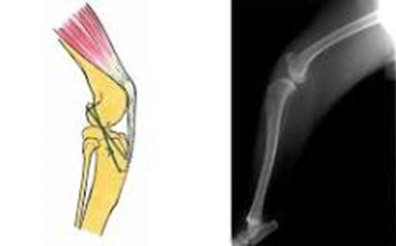

TPLO法は関節外法の時に必ず発生する骨関節炎の進行が低いといわれており、現在では前十字靭帯断裂に対する手術の第1選択法と言われています。TPLO法の原理は、脛骨の角度を調節することにより膝関節にかかる筋肉の力を変化させて前十字靭帯断裂により引き起こされる脛骨の前方変位を中和し、関節の動的な安定をもたらす手術方法です。

膝を安定化させるために膝関節内にある前十字靭帯が外傷や激しい運動などにより断裂し、跛行を呈する疾患です。これが切れると足を着地させたときに膝が沈み込むようになり、歩行困難になります。症状が進むと骨関節炎や半月板損傷が起こり、痛みを伴うようになります。 跛行(はこう)を主訴に動物病院に来院する犬の実に30%以上がこの前十字靭帯断裂と言われております。若い時期にボール投げやフリスビーをしていて切れる事も稀にありますが、年齢を重ねると前十字靭帯自体が変性し、切れやすくなります。こういった慢性断裂(Cranial cruciate disease)には、遺伝的要因や免疫学的要因、形態学的要因、生体力学的要因などがあるとされています。

靭帯の部分断裂が疑われるが関節が安定している場合には内科的保存療法(体重や運動の管理、鎮痛剤)が主体になります。一方、部分断裂でも関節が不安定な場合や完全断裂の場合には手術が必要になります。